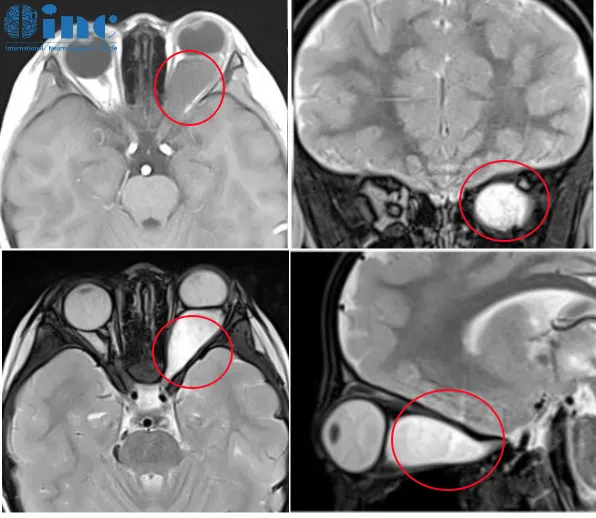

肿瘤位于脑干关键区域、与神经纤维存在危险的毗邻关系、患儿...